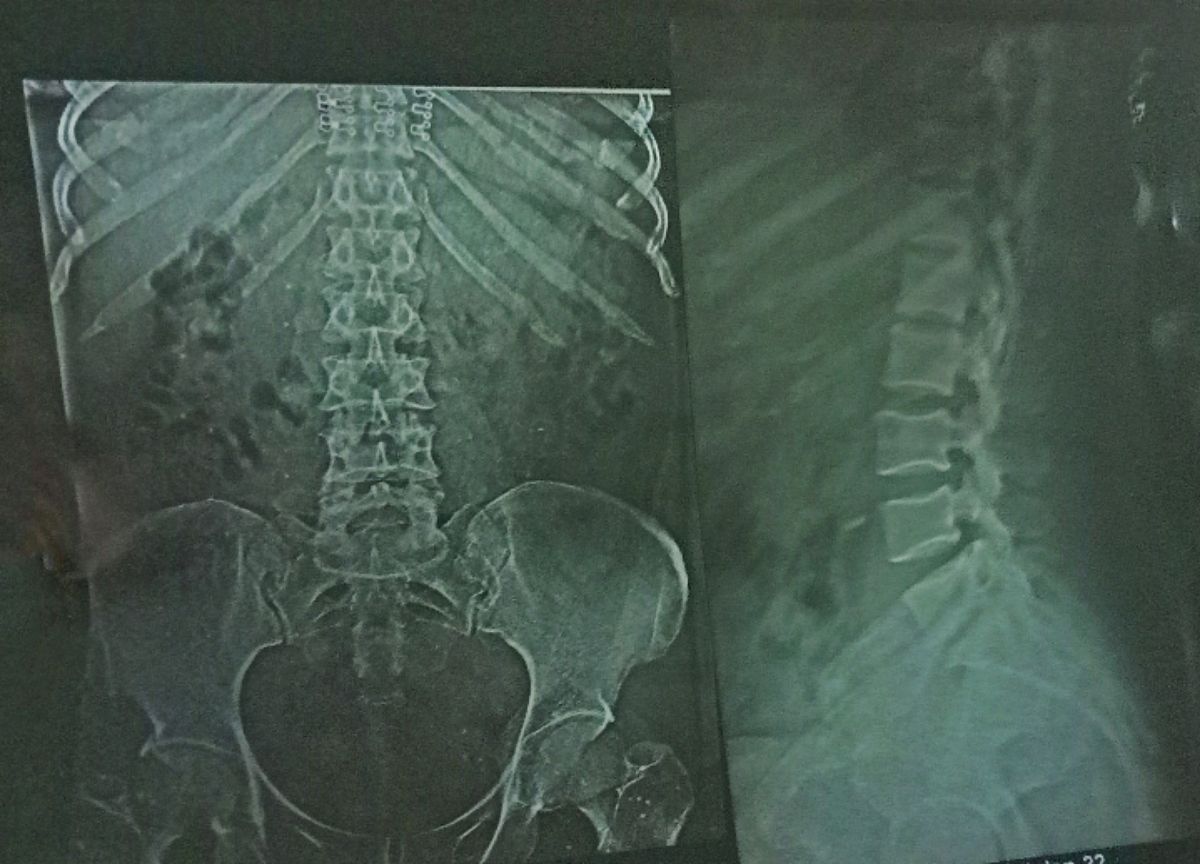

椎体成形术(percutaneous vertebral augmentation, PVA)是一种用于治疗脊柱骨折和椎体压缩性骨折的介入手术。其适应症和禁忌症如下:

1. 脊柱骨折:椎体成形术常用于治疗由骨质疏松、脊柱转移性肿瘤、骨髓瘤等引起的椎体骨折。

2. 椎体压缩性骨折:椎体成形术对于因骨质疏松、骨髓瘤等引起的椎体压缩性骨折也有很好的疗效。